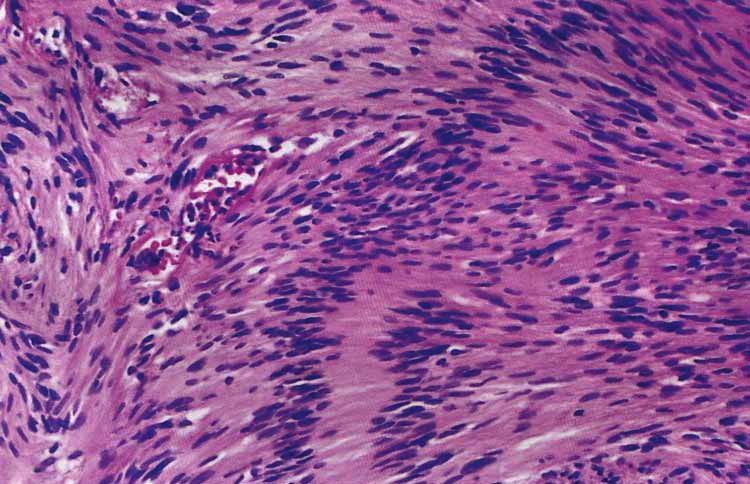

Schwannoma - tumor contains a verocay body

Schwannoma: note the Antoni A (more cellular, palisading nuclei with surrounding pink areas with rows of nuclei in parallel array called Verocay bodies) and Antoni B which has looser stroma, fewer cells, and myxoid change